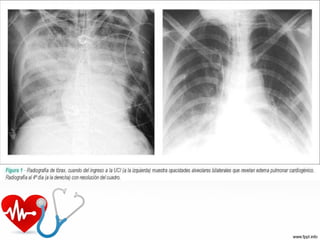

•Imagenología

RX de tórax